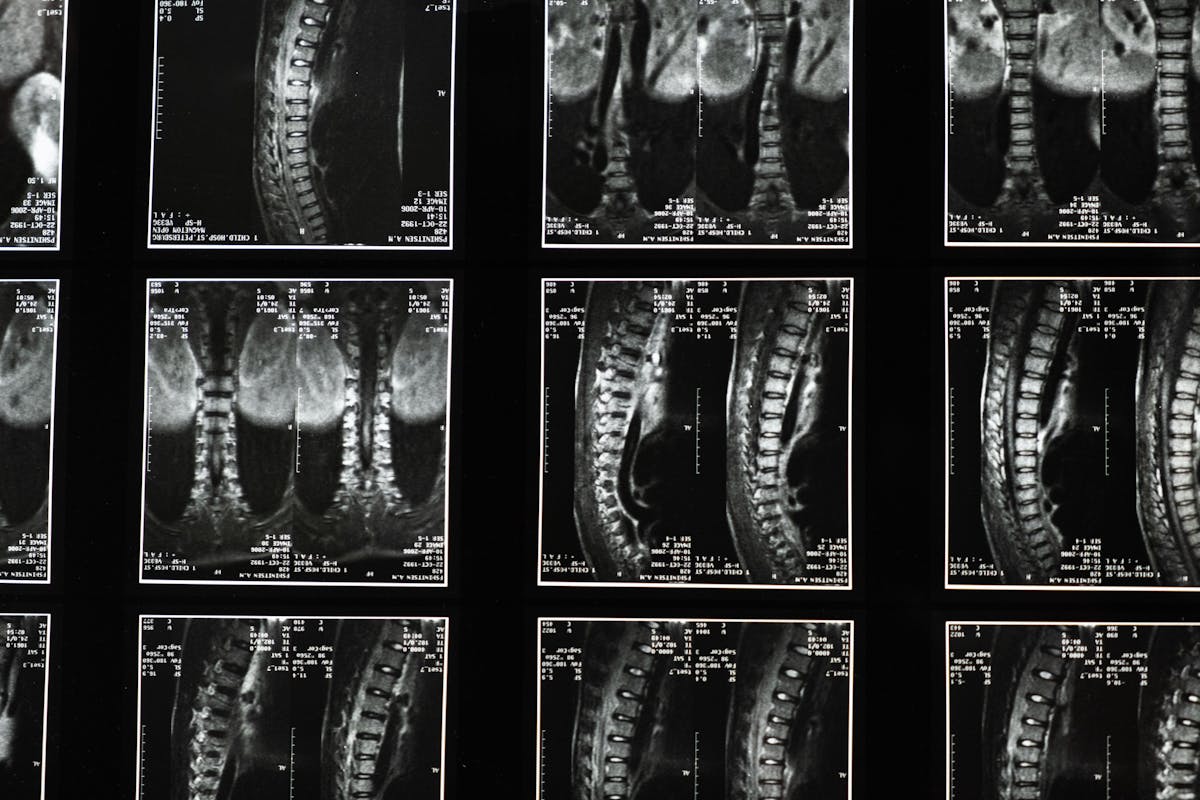

La scoliose est bien plus qu’un simple “dos courbé”. Il s’agit d’une déformation structurale de la colonne vertébrale qui provoque une courbure latérale, souvent accompagnée d’une rotation. Elle peut survenir dès l’enfance, mais aussi à l’âge adulte, notamment à cause de dégénérescences articulaires. Dans tous les cas, cette pathologie peut entraîner une gêne fonctionnelle importante, voire une perte de mobilité si elle n’est pas traitée à temps.

Le diagnostic repose sur des examens cliniques, souvent confirmés par une radiographie. On distingue plusieurs formes de scoliose : idiopathique (sans cause connue), congénitale, ou secondaire à d’autres maladies. Dans tous les cas, une prise en charge adaptée, notamment via la kinésithérapie pour scoliose, est indispensable pour limiter les conséquences à long terme.